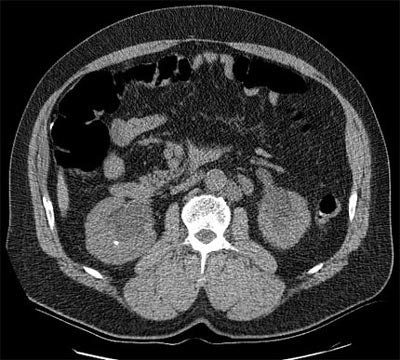

![]() |

| Seventy-year-old man with a history of metastatic cancer. Patient presented for fiberoptic colonoscopy and concurrent virtual colonoscopy to evaluate for colon cancer, and determine the primary location of metastatic disease. Virtual colonoscopy revealed bilateral hydronephrosis with renal calculi. He was subsequently diagnosed with primary bladder adenocarcinoma. Images courtesy of Dr. Greg Galdino. |